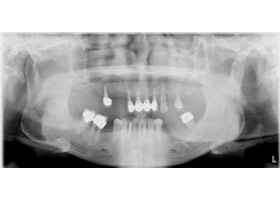

1. 治療前X光片,多處缺牙及嚴重牙周破壞。

proimages/case/Artificial_implant/all-1.jpg